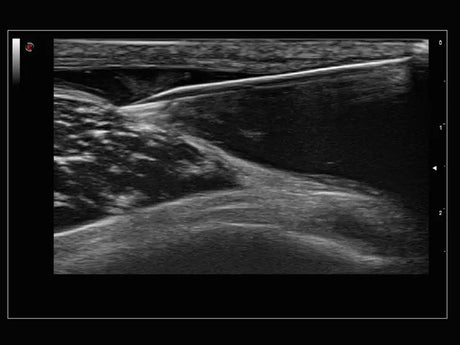

La qualité d’image est au cœur de la philosophie Esaote. Grâce à ses sondes de dernière génération et à son traitement du signal avancé, la marque permet une visualisation fine des structures anatomiques, même les plus profondes. Leurs échographes intègrent des écrans tactiles haute résolution, une interface claire et une connectivité complète, favorisant un flux de travail rapide et efficace.

Un gynécologue privilégiera un échographe offrant une résolution d’image très fine et une compatibilité avec des sondes endocavitaires. Un kinésithérapeute ou un médecin du sport recherchera plutôt un appareil portable, léger et rapide à mettre en route. Les praticiens généralistes apprécieront la polyvalence et la facilité d’entretien, tandis que les vétérinaires auront besoin d’un système robuste et facilement transportable.